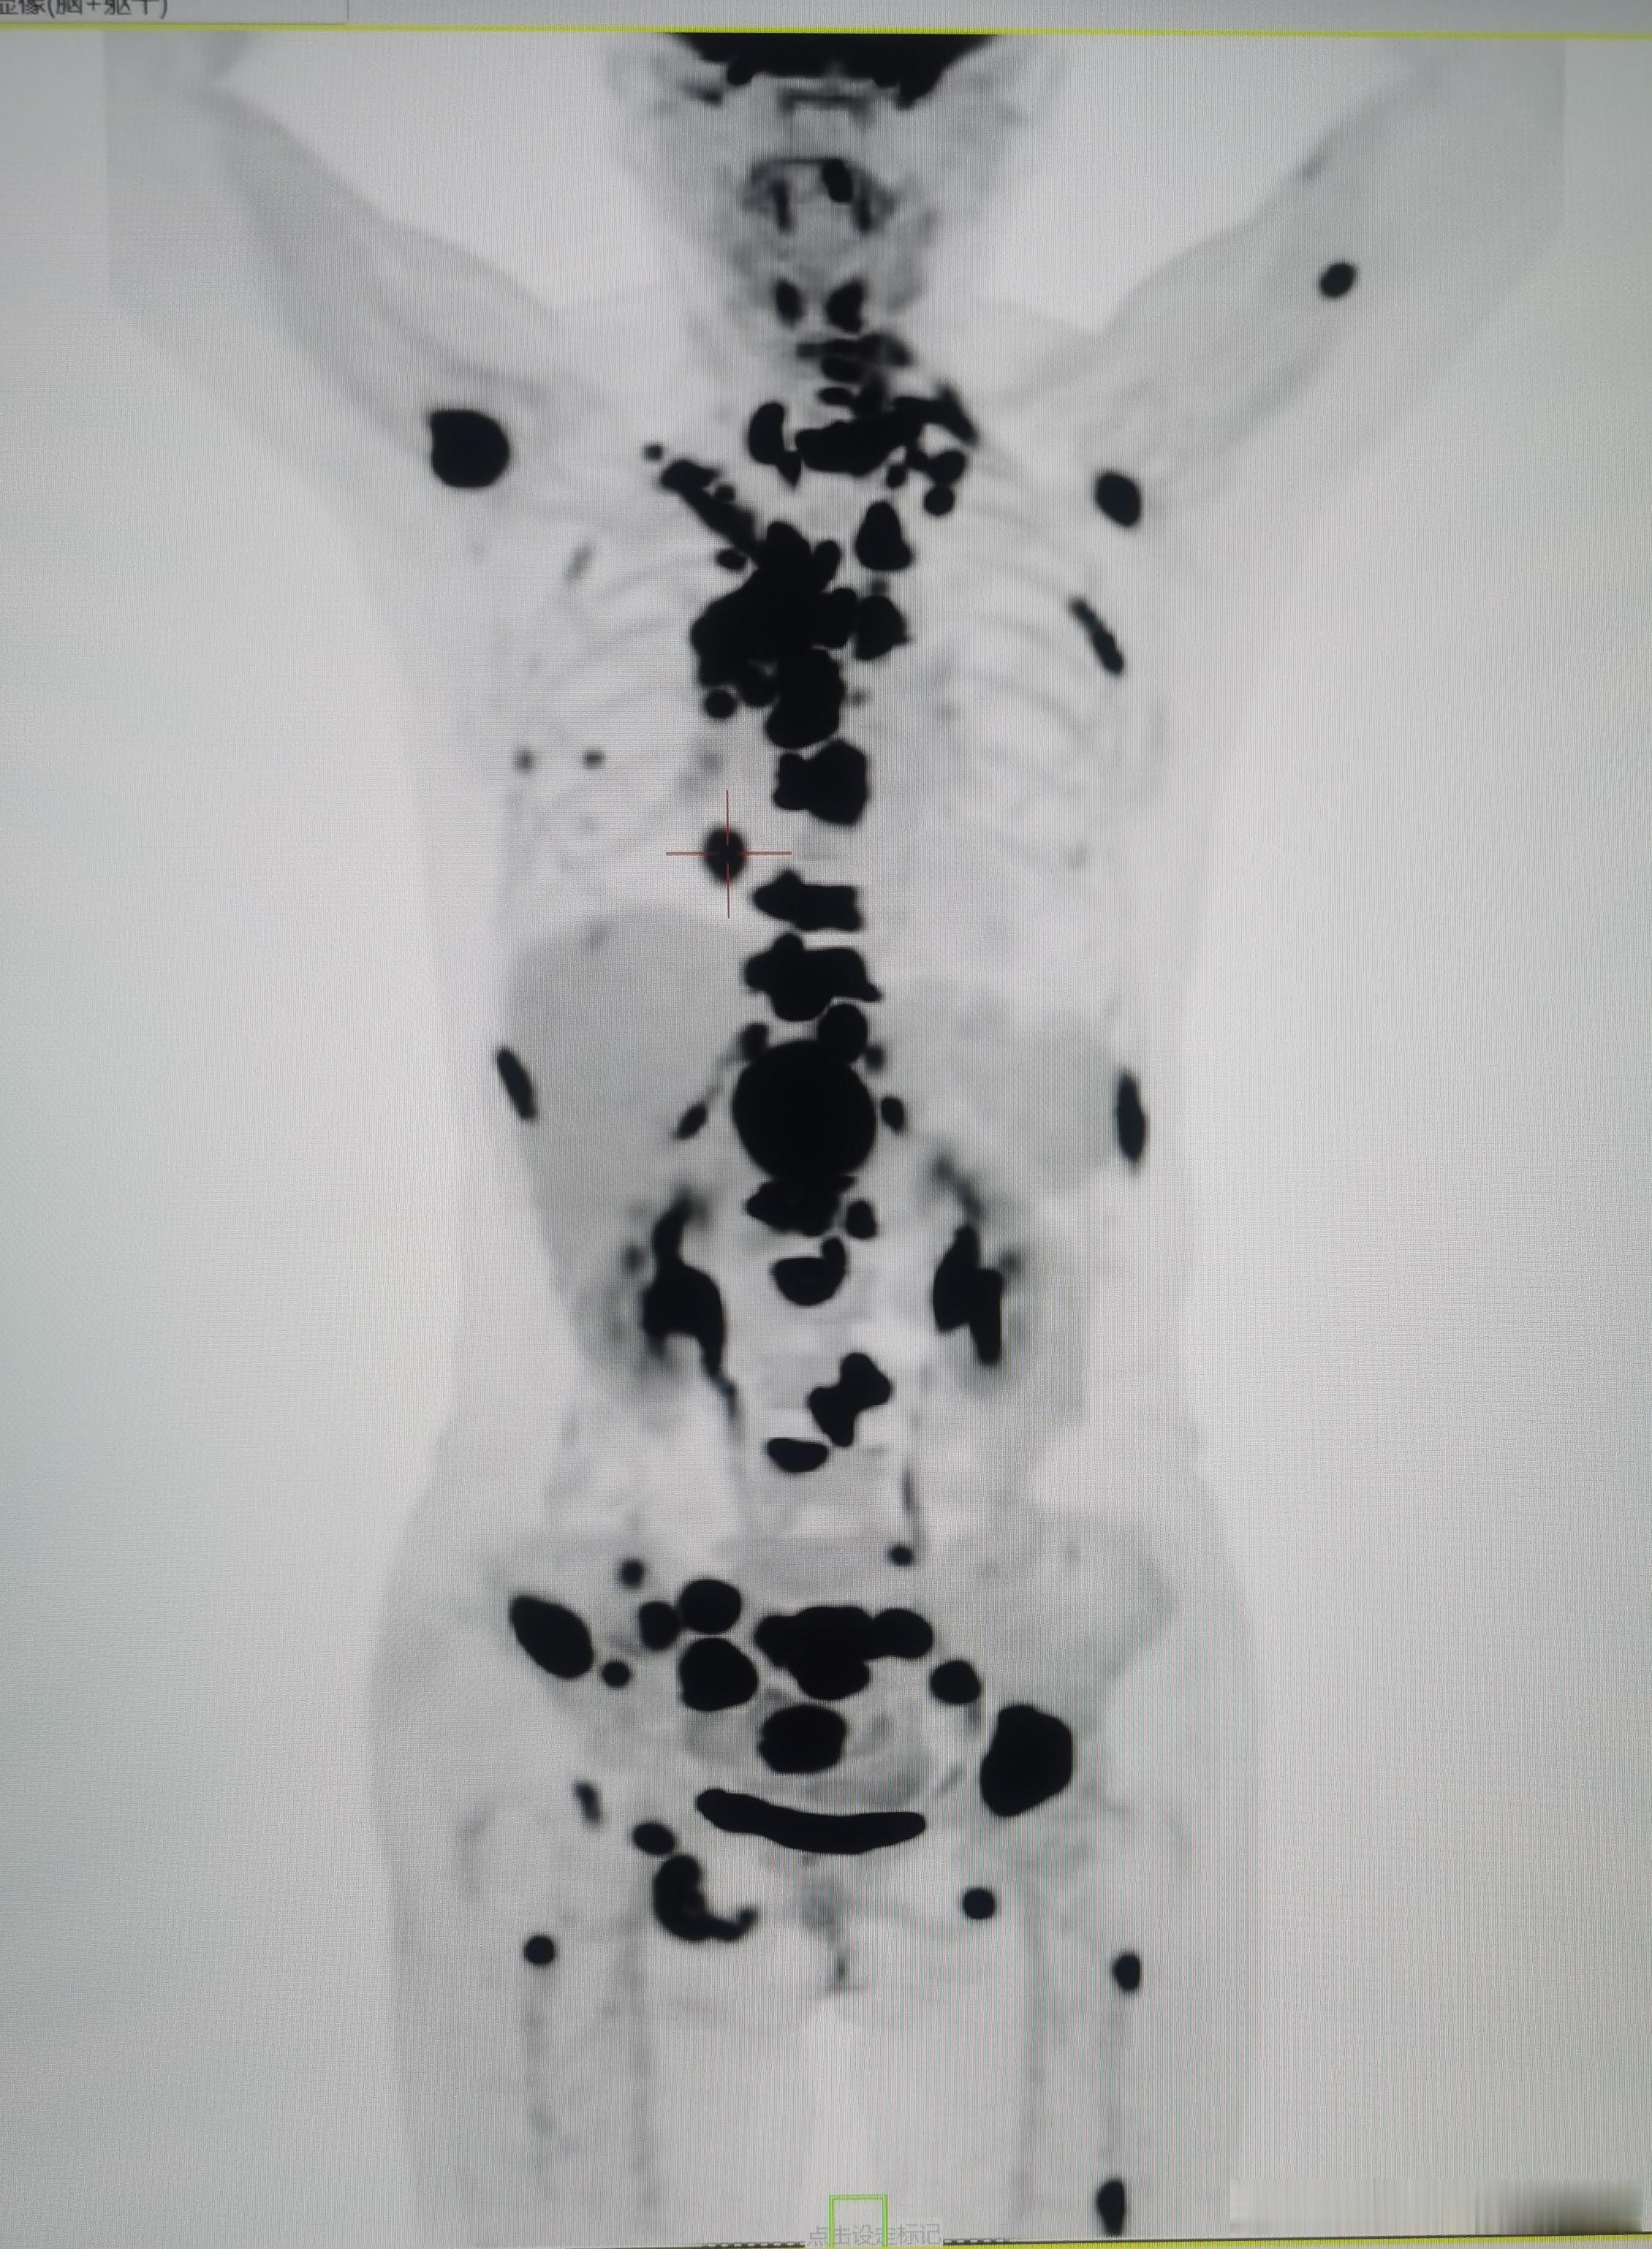

为什么非要等到肺癌全身转移才想到做PET/CT?

中国最新的数据表明:肺癌是中国恶性肿瘤发病和死亡的首位原因。发病前五位的恶性肿瘤